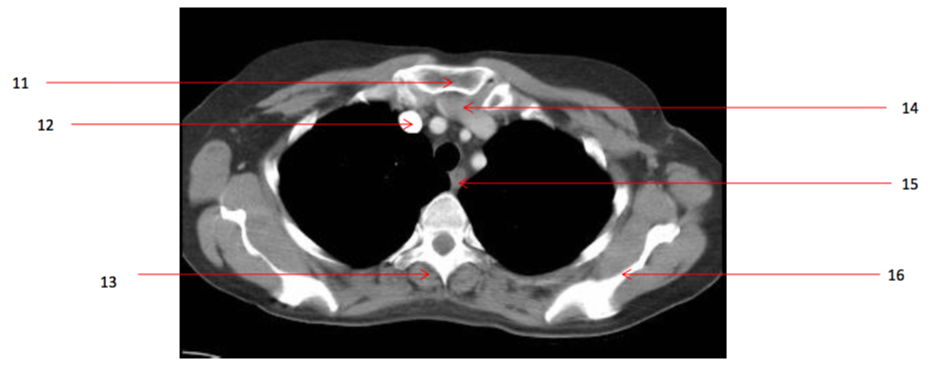

Number 1?

Rt pectoralis major muscle

Number 8?

Lt subclavian artery

Number 4?

Trachea

Number 7?

Lt common carotid artery

Number 5?

Rt subscapularis muscle

Number 9?

Lt infraspinatus muscle

Number 3?

Brachiocephalic artery